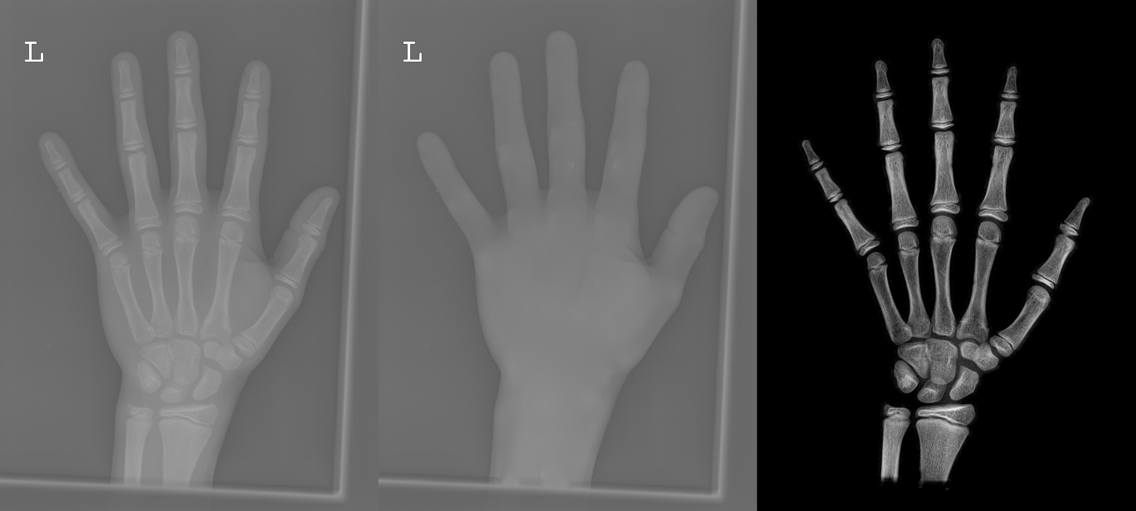

To tackle these problems, we propose to estimate the soft tissue image and bone image simultaneously without losing the linear relationship between image intensity and physical property of the imaging objects. Two examples from our method is shown in Fig. 1. The bone details are enhanced, which is theoretically guaranteed. The details of our method will be explained in later sections.

Several results from our method are shown in Fig. 7. The left column is the original input image. The right two columns are the soft tissue and bone image, respectively. It can be told that the soft tissue image is smooth as we assumed. Meanwhile, the bone image has better image contrast as desired. Moreover, our method can reach real-time performance on these X-ray images. The running time of our method on these images is reported in Table I.

In each panel of Fig. 10, the input image (left) is decomposed into soft tissue (middle) and bone image (right) by our method. Although we only show the first ten images from the data set, the results for the rest images are similar.

The bone images have better image contrast since the parameter is theoretically guaranteed. Such enhancement can also be directly told by radiologists. Such enhancement is good for bone diagnosis in practical applications.